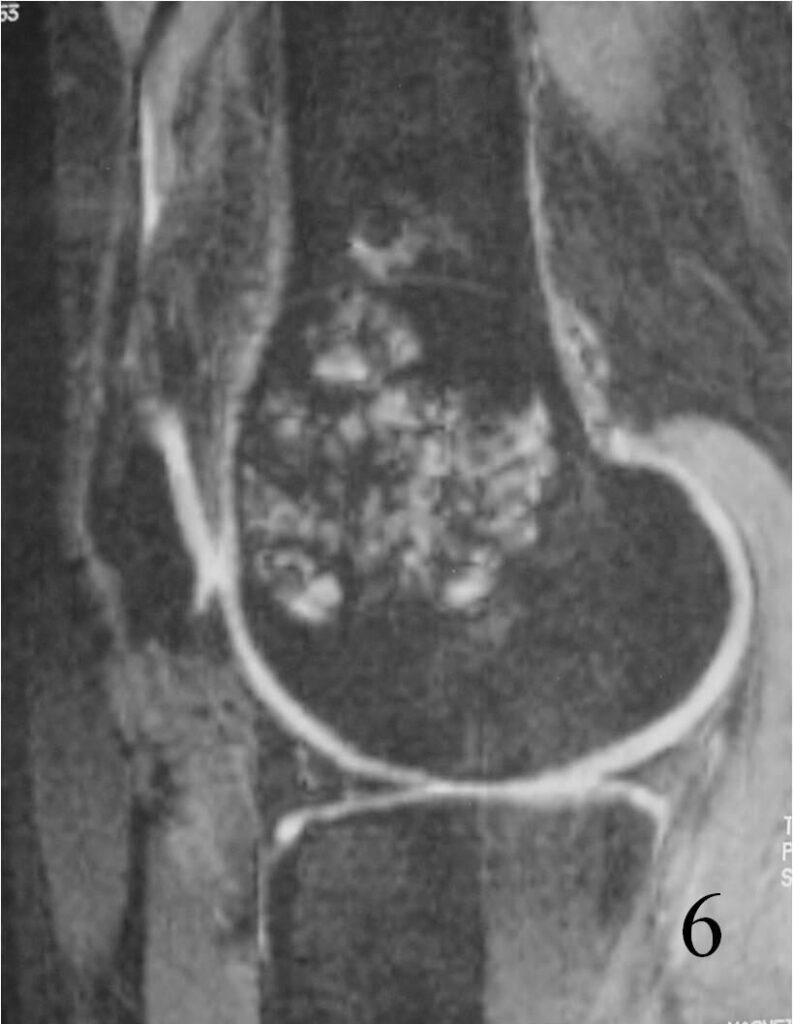

- They will be low to intermediate on T1-weighted images, and intermediate to high on T2-weighted images (Fig. 4, 5, 6)

Fig. 6 Sagittal T2 FS MRI shows high and low signal areas (heterogeneous)